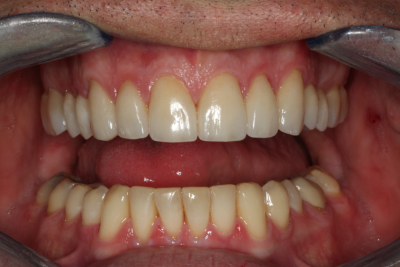

Esthetics, phonetics, and functionを確認した後、最終的な修復を行う準備が整いました。 プロビジョナルレストレーションの写真と印象がラボに渡され、プロビジョナル段階で調整した審美性と咬合を複製し、Darrenの最終修復物に情報を伝達しました。 納品日までに、すでに機能的な問題を診断・治療し、プロビジョナルで治療計画を検証しています。

私たちの目標のひとつは、下顎前歯の準備をせずに、適切な前歯部誘導を達成することでした。 幸いなことに、矯正とダイレクトボンディングの組み合わせで十分すぎるほどの結果が得られたので、今回は下顎弓の修復を見送ることができました。 繰り返しになりますが、私たちの目標は、可能な限り最良の結果を得るために、最小限の歯科治療を行うことです。 時には、包括的な歯科治療を行うために、かなりの量の治療を行うこともありますが、できるだけ多くの歯質を保存するために、保守的であることに挑戦することが重要なのです。

ダレンとの協力により、咬合安定の5つの要件を得るために必要な治療を提供することができました。 現在、彼はすべての歯で安定したストップ、機能の包絡線と調和した前方誘導、前歯が突出した場合の即時後方排除、および作業側と平衡側の突出の干渉をもはや持っていない。